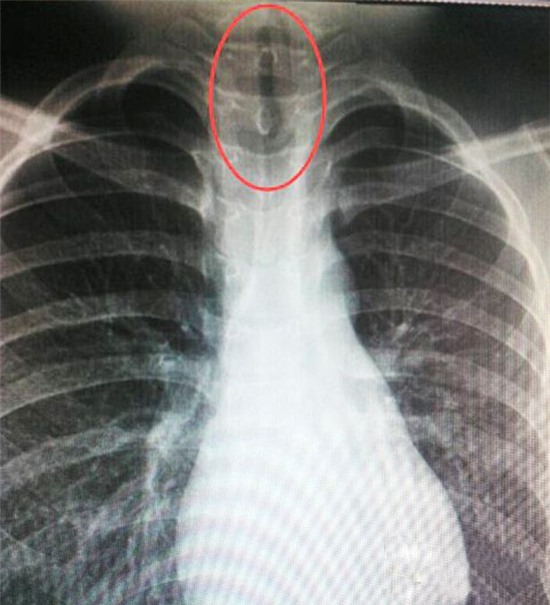

Old  Default Kinh hoàng khi chứng kiến đỉa kẹt trong ống thở.

Cậu bé Xiabo Chien liên tục kêu đau họng và choáng váng. Thật không ngờ đó là hậu quả của việc dừng lại uống nước bên hồ ở vệ đường.

Bà Xiang Tung, 33 tuổi, mẹ của Xiabo cho biết: “Lúc đầu chúng tôi tưởng thằng bé bị cúm vì nó nói nó bị choáng và đau họng. Thằng bé không nói đã dừng lại uống nước ao bên đường nên không ai nghĩ có thể nó đã nuốt phải cái gì đó”.Vì nghĩ con ốm xoàng, gia đình cho Xiabo uống thuốc rồi để cậu nghỉ ngơi. Nhưng tình hình mỗi lúc một tệ hơn nên cậu bé được đưa đến bệnh viện.Tại đây cậu bé 11 tuổi được đưa đi chụp X-quang và kết quả phim chụp khiến nhiều người hoảng hốt: Một con đỉa cỡ 7cm bị mắc kẹt ở cổ họng.

Đại diện bệnh viện cho biết: “Chúng tôi phát hiện ra rằng cậu bé đã nuốt phải ấu trùng đỉa. Có thể ấu trùng đã tìm cách đi lên được phía cổ họng để lấy không khí, nó cứ thế “lớn dần” tới 7 cm. Mỗi khi con đỉa ngọ nguậy sẽ làm kẹt đường thở và khiến cậu bé không còn tỉnh táo.

Thật may là chưa nhiễm trùng. Các bác sĩ có thể lấy con đỉa ra không mấy phức tạp. Xiabo sau đó đã cảm thấy khá hơn.